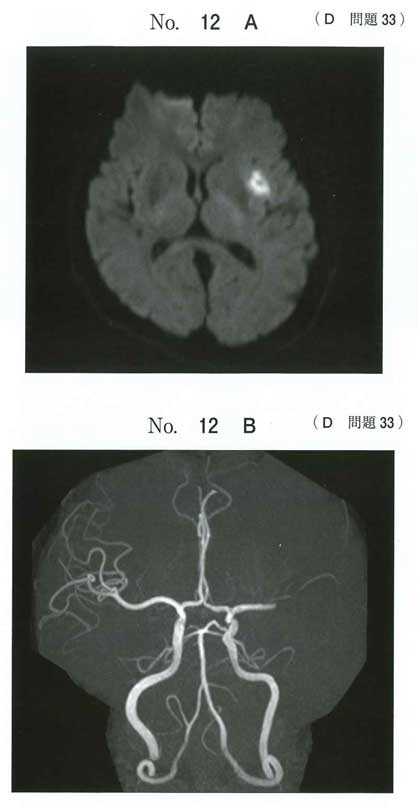

正解: c

主幹動脈閉塞の急性期脳梗塞では 血栓回収療法が第一選択